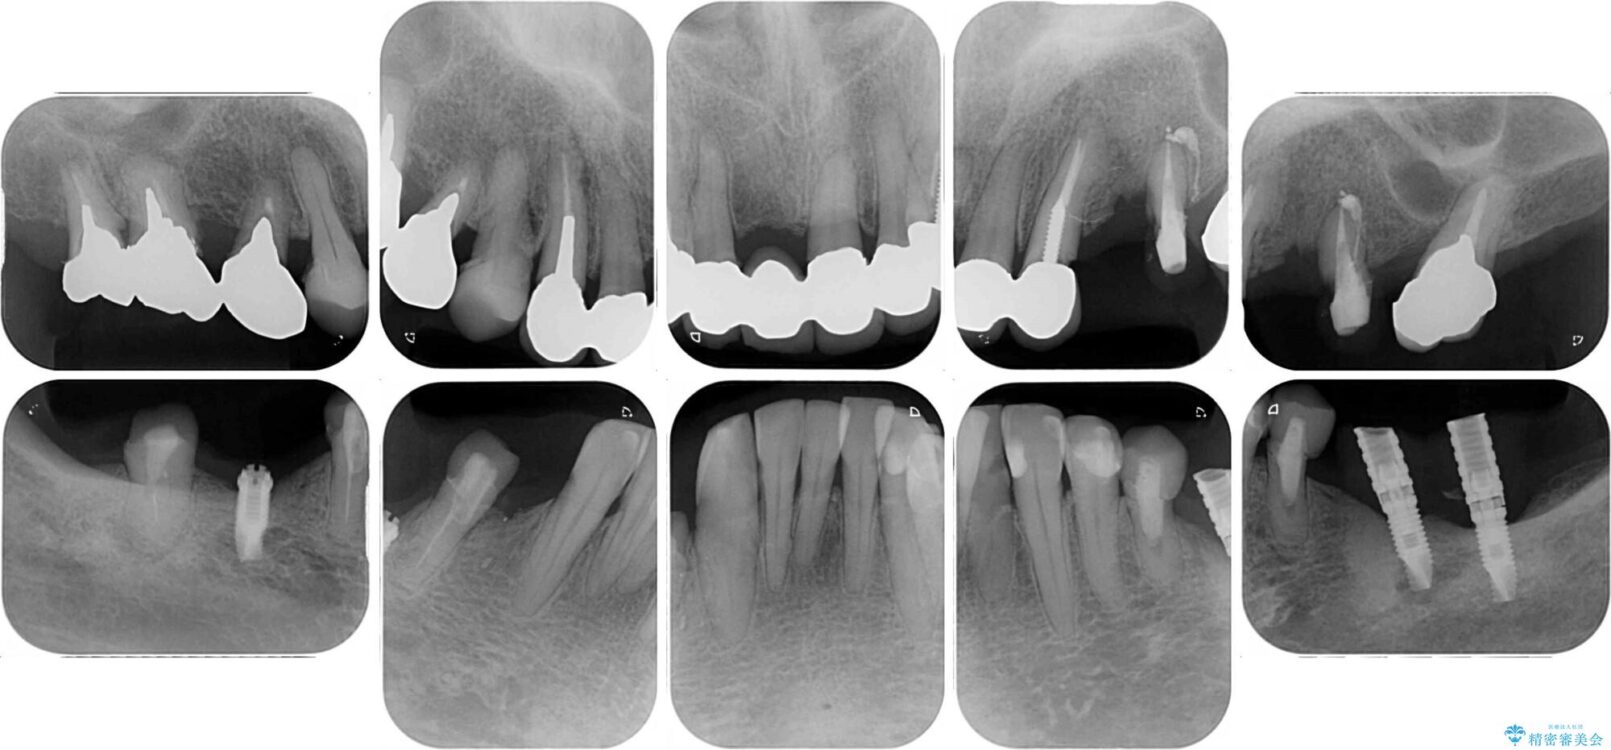

治療前

• 放置したインプラントとインビザライン 全顎リカバリー治療 治療前画像

治療途中